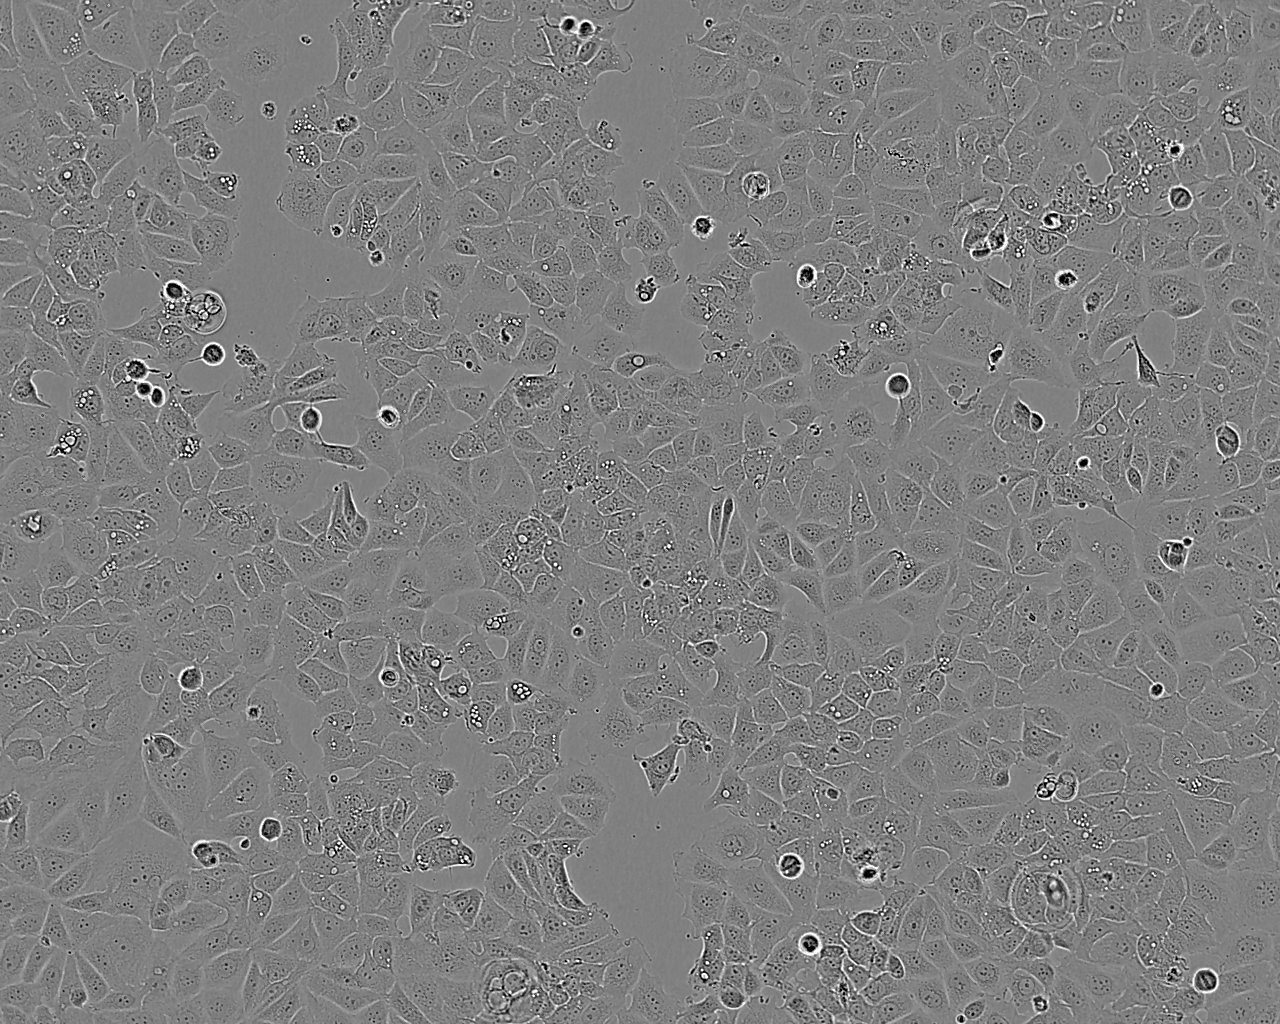

Images

Established from the pleural effusion from a 69 year female caucasian suffering from a breast adenocarcinoma. Cells exhibit some features of differentiated mammary epithelium including oestradiol synthesis and formation of domes. Cells may carry B or C type retrovirus and are considered to represent a category 2 pathogen (P2 containment). Cells express both the wild type and variant oestrogen receptors as well as progesterone receptor. The cells should be handled under laboratory containment level 2.

Subculture Routine

Split sub-confluent cultures (70-80%) 1:2 to 1:6 i.e. seeding at 2-4x10,000 cells/cm² using 0.05% trypsin or trypsin/EDTA; 5% CO₂; 37°C.